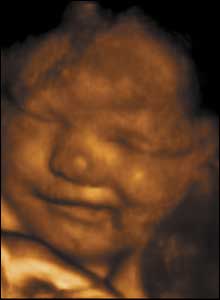

34 týdnů, 34 cm

Ačkoli se děti první 4 až 6 týdnů po narození neusmívají, plod v děloze ano. Možná proto, že děloha je teplá, příjemná, chrání před hlukem a ostrým světlem.